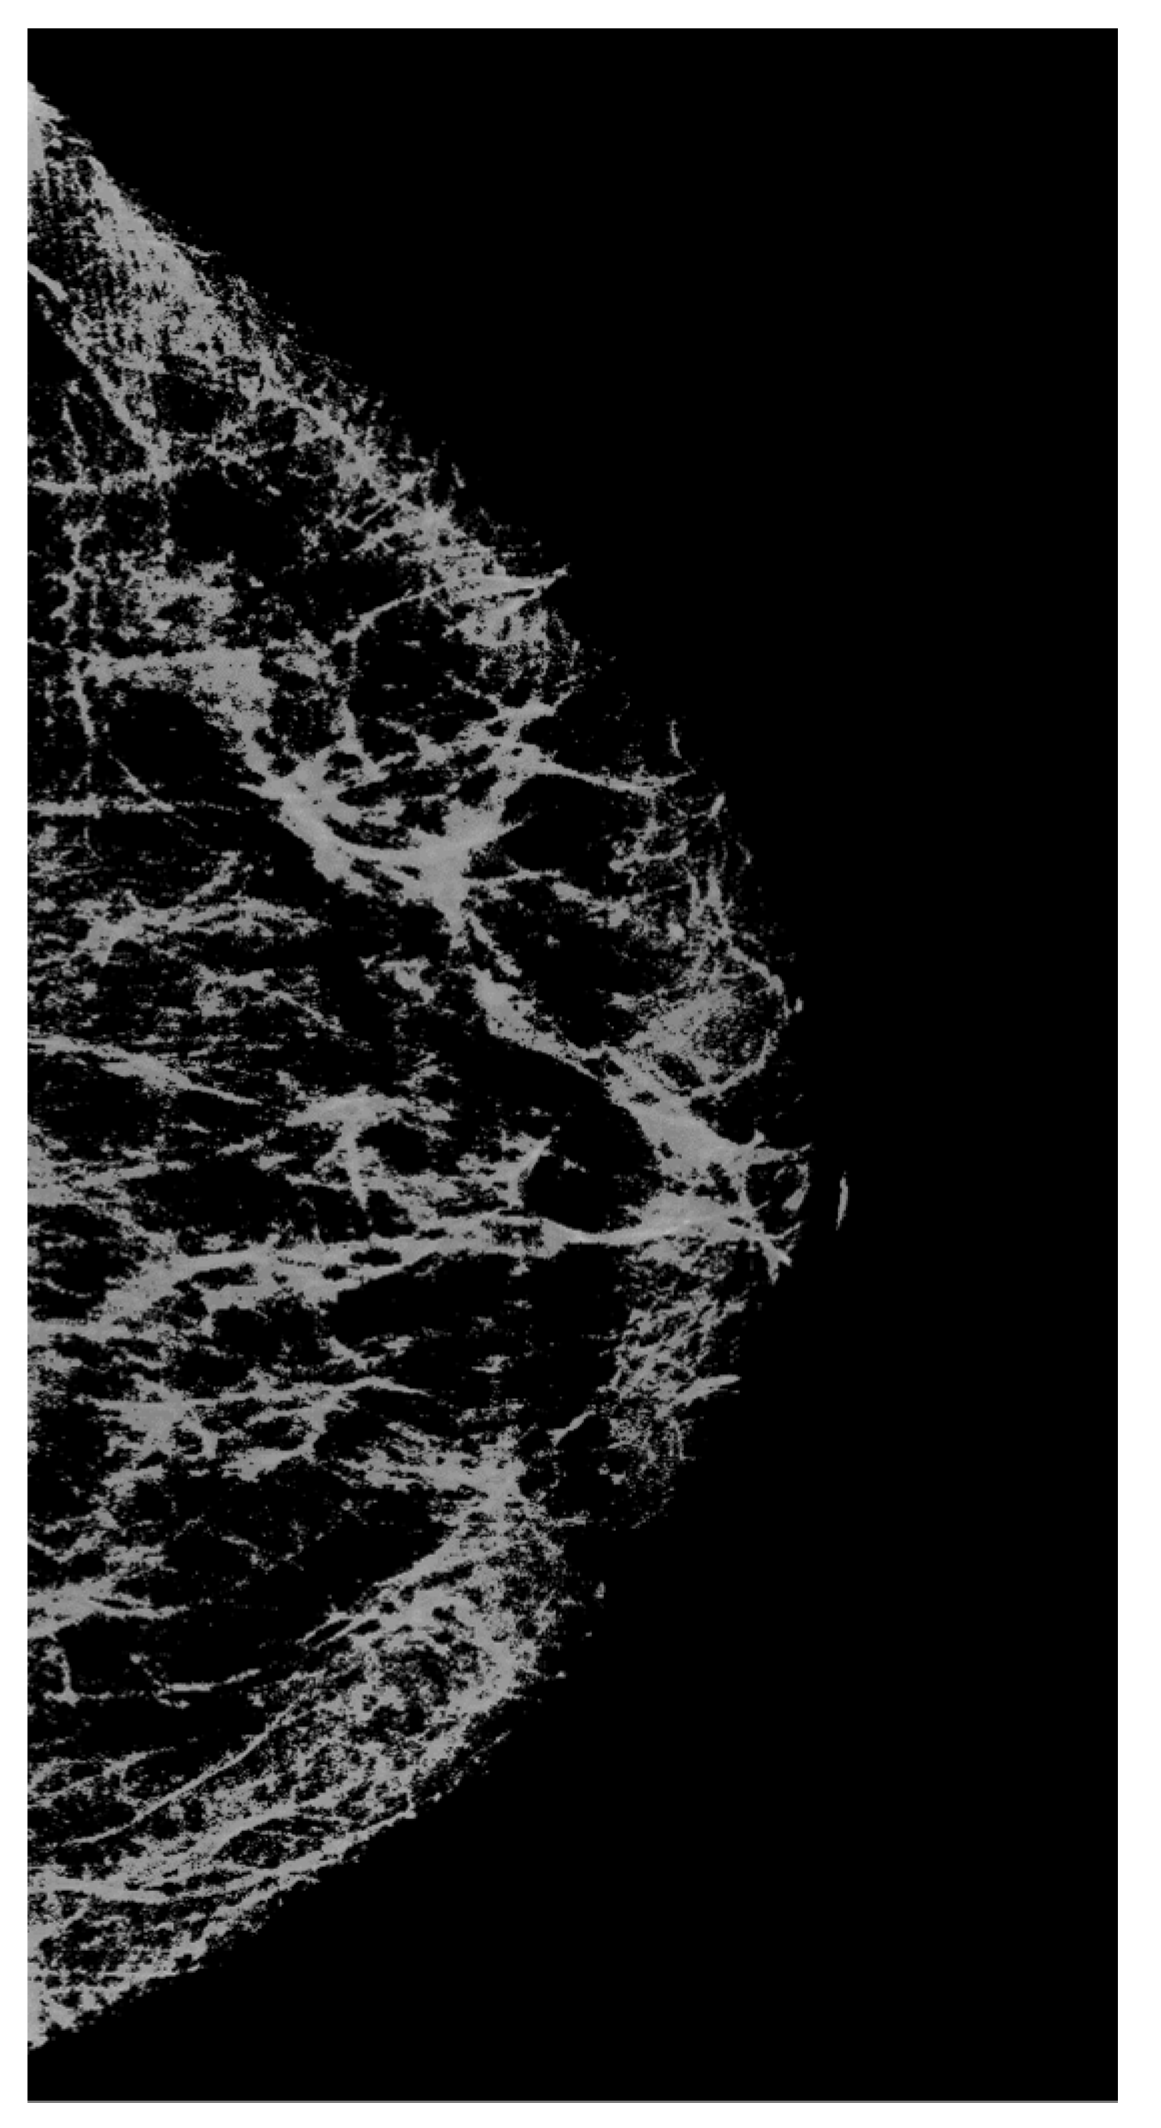

| Figure 1a | Original image | 18.72 | 10.41 |

| Figure 1b | Original image | 14.34 | 9.77 |